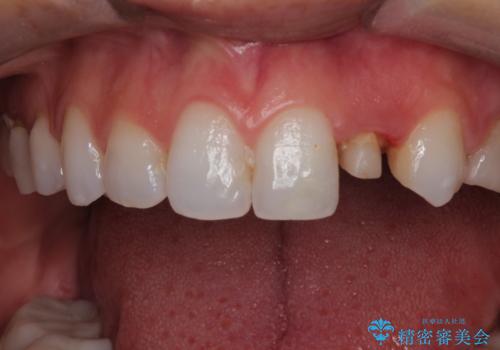

前歯の被せ物をやり替えたい

- 以前に被せ物の治療した箇所に汚れが溜まりやすいことを主訴に来院されました。

矯正治療を行なったのち、オールセラミッククラウンにて修復しております。

矯正治療はインビザラインで行なっております。